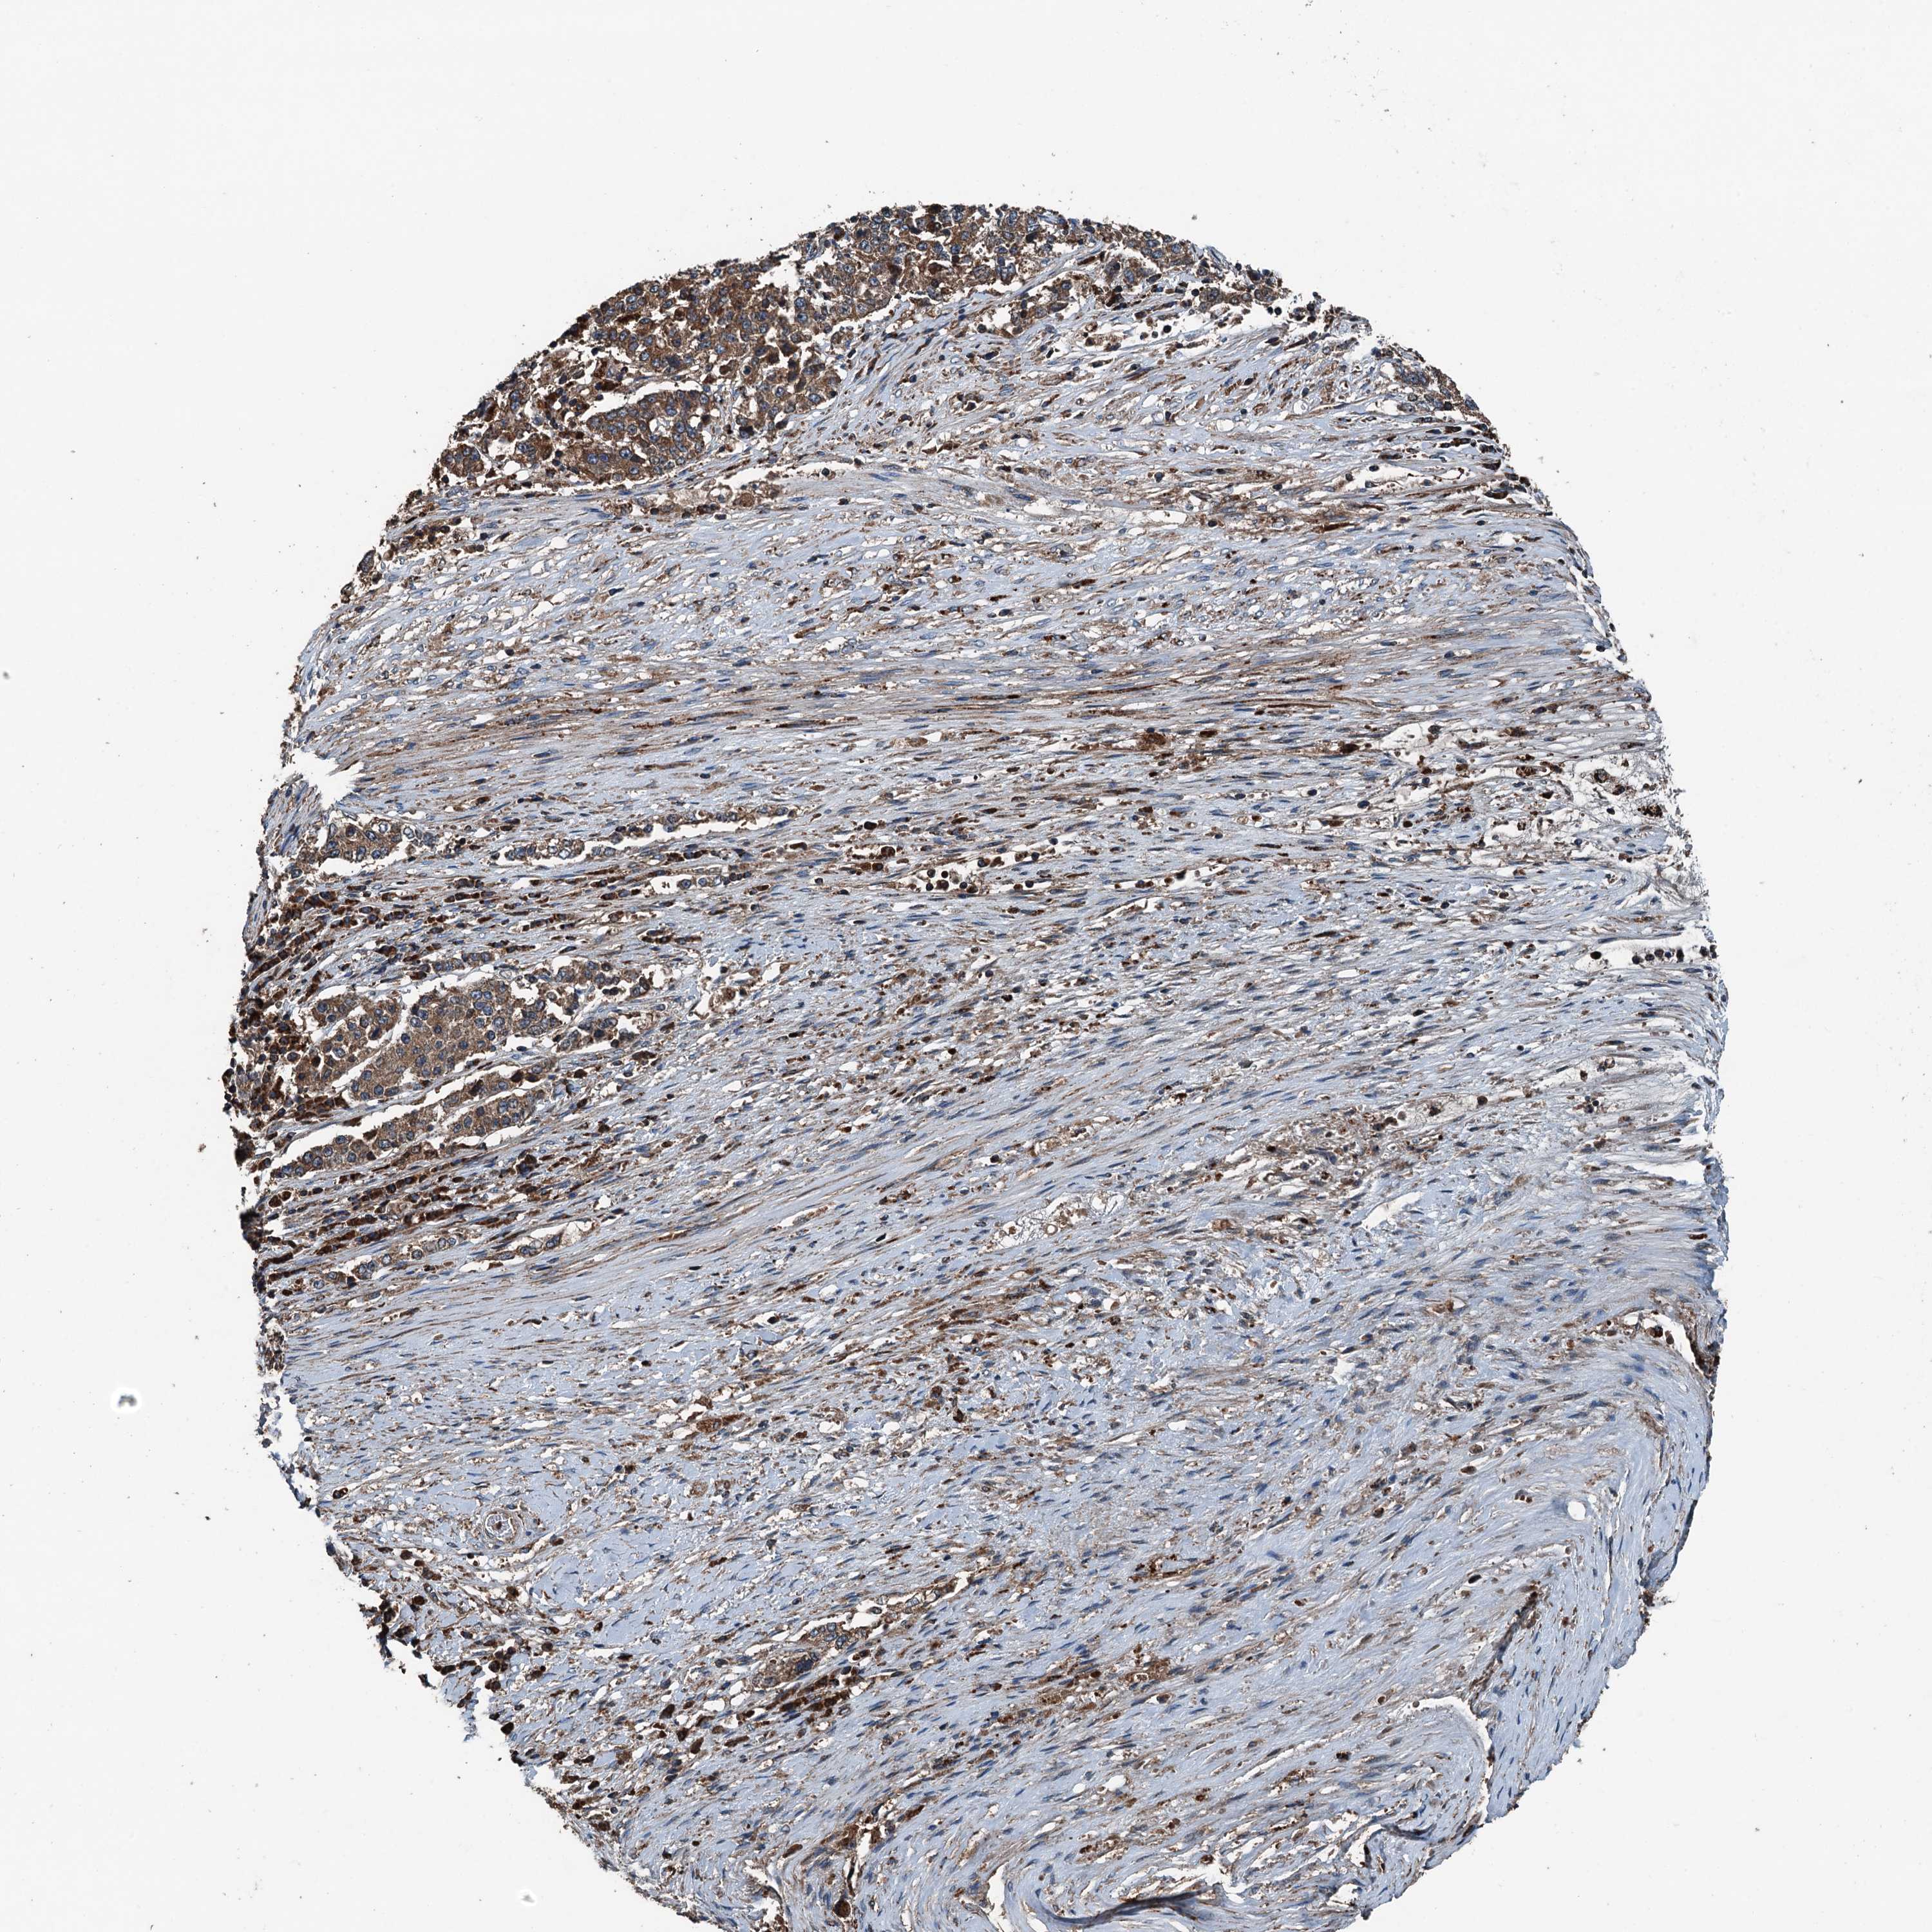

STOMACH CANCER - Protein expressioni

A mouse-over function shows sample information and annotation data. Click on an image to view it in a full screen mode. Samples can be filtered based on level of antibody staining by selecting one or several of the following categories: high, medium, low and not detected. The assay and annotation is described here.

Note that samples used for immunohistochemistry by the Human Protein Atlas do not correspond to samples in the TCGA dataset.

Antibody stainingi

Antibody staining in the annotated cell types in the current human tissue is reported as not detected, low, medium, or high, based on conventional immunohistochemistry profiling in selected tissues. This score is based on the combination of the staining intensity and fraction of stained cells.

Each image is clickable and will lead to virtual microscopy that enables deeper exploration of all samples and also displays staining intensity scores, fraction scores and subcellular localization as well as patient and tissue information for each sample.

Antibody HPA041227

Staining

High

Medium

Low

Not detected

Intensity

Strong

Moderate

Weak

Negative

Quantity

>75%

75%-25%

<25%

None

Location

Nuclear

Cytoplasmic/membranous

Cytoplasmic/membranous,nuclear

Adenocarcinoma, NOS

Adenocarcinoma, High grade